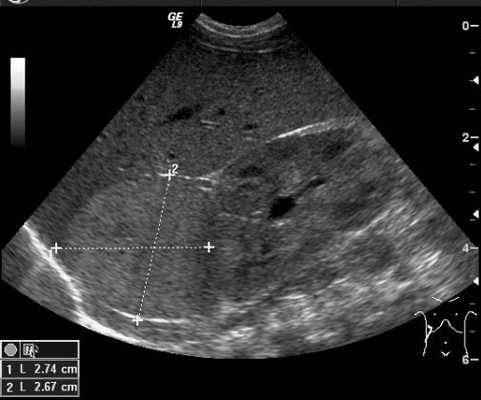

Ультразвуковое исследование

Ультразвуковой метод исследования позволяет выявить наличие опухоли и ее расположение по отношению к внутренним органам. УЗИ позволяет оценить степень местного и отдаленного распространения злокачественного процесса и выявляет метастатическое поражение печени и лимфатических узлов (рис. 4).

Рис. 4. УЗИ образования правого надпочечника